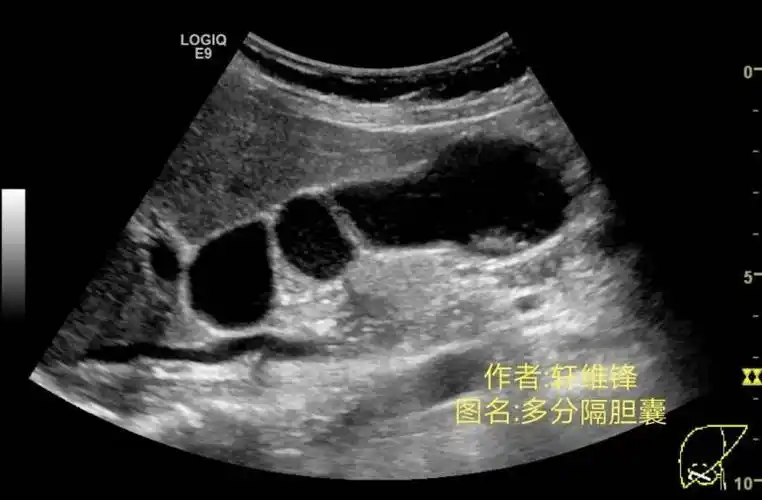

图3-19 胆囊腺肌症(节段型)